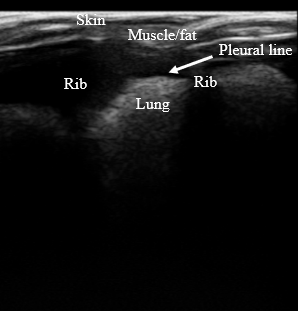

The design of the lung phantom was validated by accurately mimicking the anatomy of in vivo lungs (Figure 2), replicating the visual appearance of the lungs in US (Figure 3), and maintaining accurate relaxation values in MRI to reported tissue values. A summary of the TMMs used and relaxation parameters are shown in Table 1. Comparison between the muscle/fat material and in vivo muscle/fat tissue demonstrated a 2% difference in T1 relaxation and a 19% difference in the T2 relaxation at 4.7T.

Figure 3: Sagittal ultrasound image of the constructed phantom.